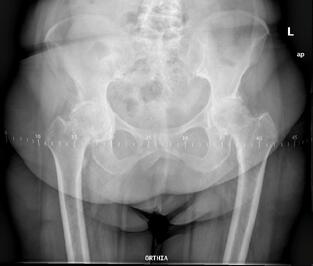

Το πρώτο βήμα κατά τη λήψη της απόφασης για την αντικατάσταση ισχίου είναι να συναντήσετε τον χειρουργό σας για να δείτε εάν είστε υποψήφιος για χειρουργική επέμβαση ολικής αρθροπλαστικής ισχίου. Ο χειρουργός σας θα πάρει το ιατρικό ιστορικό σας, θα κάνει μια φυσική εξέταση και θα ζητήσει ακτινογραφία του ισχίου σας. Ακόμα κι αν ο πόνος είναι έντονος και οι ακτινογραφίες δείχνουν προχωρημένη αρθρίτιδα της άρθρωσης, η πρώτη γραμμή θεραπείας είναι σχεδόν πάντα μη χειρουργική. Αυτό περιλαμβάνει απώλεια βάρους εάν χρειάζεται, πρόγραμμα άσκησης, αντιφλεγμονώδη φάρμακα, ενέσεις ή νάρθηκες. Εάν τα συμπτώματα συνεχιστούν παρά αυτές τις θεραπείες και με επιβεβαιωτικές ακτινογραφίες, τότε μπορείτε να εξετάσετε το ενδεχόμενο χειρουργικής επέμβασης.